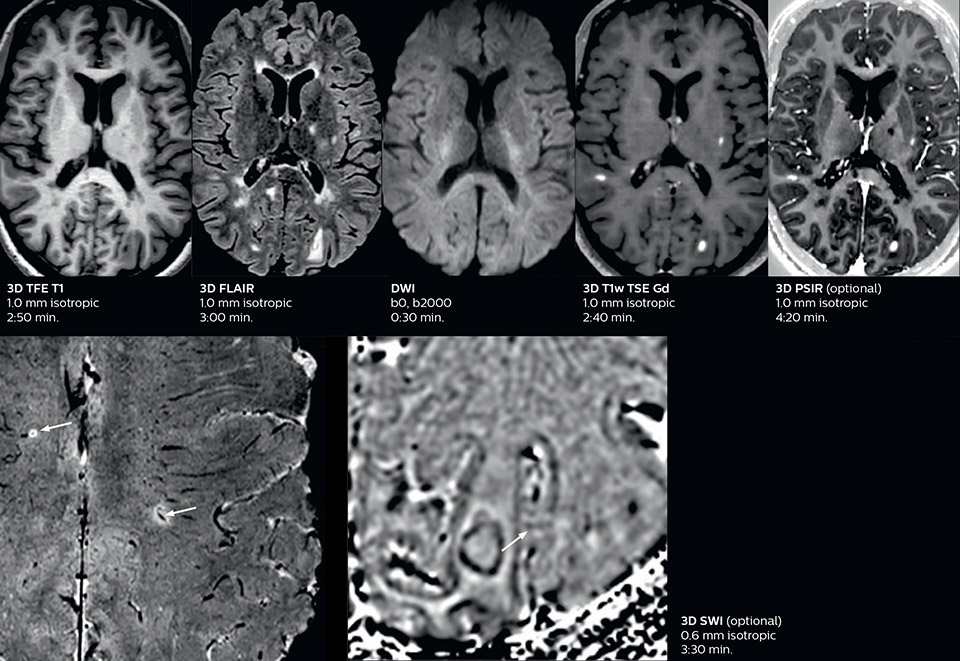

Fast MS protocol with optional sequences

The abbreviated MS protocol for brain is only around 9 minutes, so in case of suspected multiple sclerosis, one or two more advanced sequences may be added, such as PSIR (phase sensitive inversion recovery) or susceptibility-weighted sequences to help us make more confident diagnoses in these inflammatory cases.

In this example, the optional 3D multishot susceptibility weighted sequence with 0.6 mm isotropic voxels is 2 lesions with a central vein sign (arrows) and one lesion with a phase-rim sign (arrowhead). The total scan time, including SmartBrain and axial PD/T2 3mm, is 11:10 min. and is 18:30 min. with the optional 3D PSIR and 3D SWI multishot included.

3D TFE T1

3D FLAIR

DWI

3D T1w TSE Gd

3D PSIR

3D SWI

“In multiple sclerosis patients, we increasingly include a multishot susceptibility sequence [3] in our routine cases, thanks to the shorter scan times. Our abbreviated MS protocol for brain is around 8 to 9 minutes, so we can ask for one or two additional sequences to visualize the central veins, or to get an additional contrast to better depict posterior fossa lesions. In cases of white matter lesions of unknown significance on FLAIR images, for example when we see high signal hyperintensities in the brain, we can add on more advanced sequences such as PSIR (phase sensitive inversion recovery) or susceptibility-weighted sequences to help us in distinguishing between MS and nonspecific or vascular abnormalities in these inflammatory cases.”